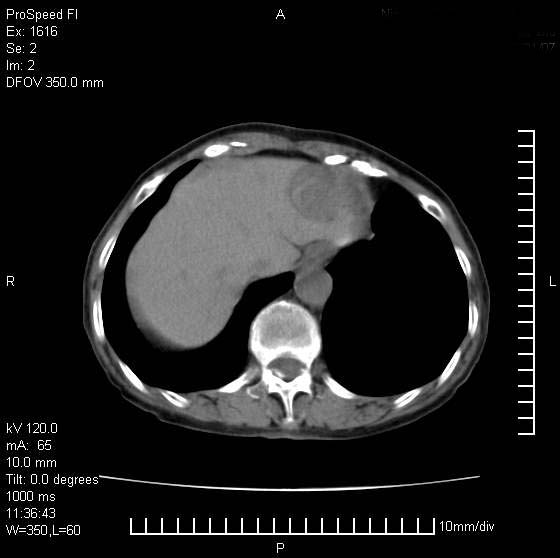

患者无明显临床症状,肝左叶发现一个圆形密度不均的低密度灶,边界较清楚,大小37x45mm,ct值35-70,患者犹豫做增强,如有增强片,我再发上,现先请各位老师会诊.

左肝外叶可见较大圆形低密度影,病灶可见较光整清晰边界,病灶内可见多量条状稍高密度影,右肝前叶亦可见圆形结节状低密度影,边界清晰,密度均匀,考虑1肝多发囊肿,左肝囊肿内出血2肝包虫病3左巨块型肝癌出血合并右肝转移或合并右肝囊肿

有可能不是一个病灶,毕竟层面太靠上,

病灶内高密度影,从ct值上看是血的密度还是某种纤维组织呢?似乎有内缘有包膜,肝脏各叶比例略失调,脾脏有点大.

hcc(巨块型)伴出血,突破肝包膜,肝胃韧带内,腹主动脉旁淋巴结转移;肝硬化